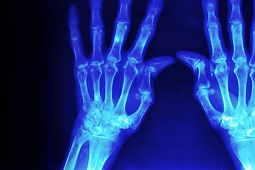

Reumatoidalne zapalenie stawów